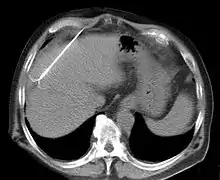

يمكن استخدام الاستئصال الراديوي لعلاج أورام الرئة والكبد والكلية والعظم، إضافة إلى عدد من أعضاء الجسم الأخرى بشكل أقل شيوعًا. عند تأكيد تشخيص الورم، يوضع مسبار الاستئصال الراديوي الشبيه بالإبرة داخل الورم. تؤدي موجات الراديو التي تعبر خلال المسبار إلى زيادة الحرارة ضمن النسيج الورمي ما يؤدي إلى تخريب الورم. يمكن استخدام الاستئصال الراديوي على الأورام الصغيرة، إن كانت هذه الأورام ناشئة من العضو ذاته (الأورام البدئية) أو منتشرة إلى العضو (انتقالات ورمية). تعتمد قابلية كل ورم على الاستجابة للاستئصال الراديوي على عدد من العوامل.[4][5][6]

يمكن إجراء الاستئصال الراديوي كإجراء خارجي، على الرغم من الحاجة إلى بقاء المريض في المشفى لفترة وجيزة. يمكن دمج الاستئصال الراديوي مع العلاج الكيميائي موضعي التوجيه لعلاج ورم الخلية الكبدي (ورم بدئي في الكبد). تستخدم طريقة وصلت إلى المرحلة الثالثة من التجارب السريرية الحرارة طفيفة الارتفاع الناتجة عن مسبار موجات الراديو لتفعيل أدوية العلاج الكيميائي المركزة من الجسيمات الشحمية الحساسة للحرارة في الحواف حول النسيج المستأصل بموجات الراديو كعلاج لورم الخلية الكبدية (إتش سي سي). يمكن استخدام الاستئصال الراديوي أيضًا في علاج سرطان البنكرياس وسرطان الطرق الصفراوية.[7]